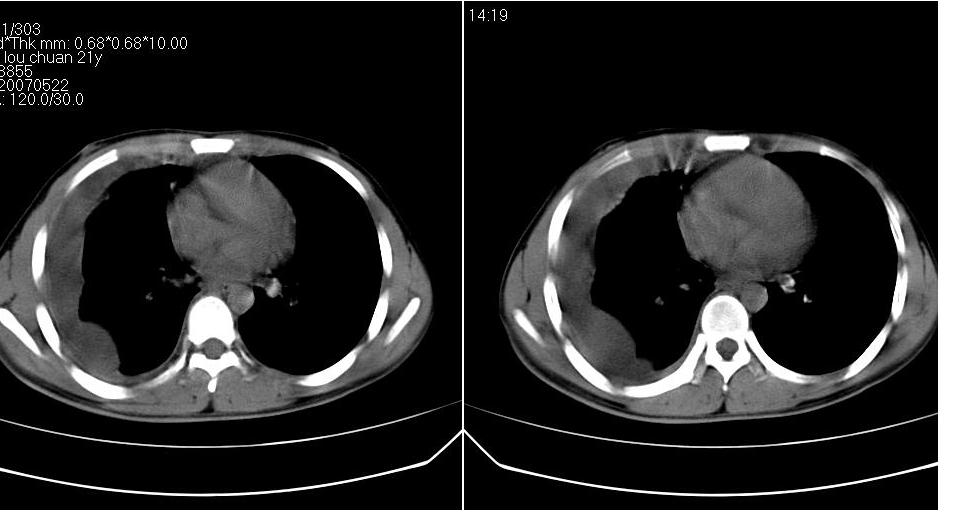

男 21岁,胸闷。

右侧包裹性积液(结核性可能大)。

右侧胸腔积液,部分呈垂滴状,包裹了,最常见的原因是结核引起的

右侧包裹性胸腔积液,考虑1:结核,2:胸膜间皮瘤